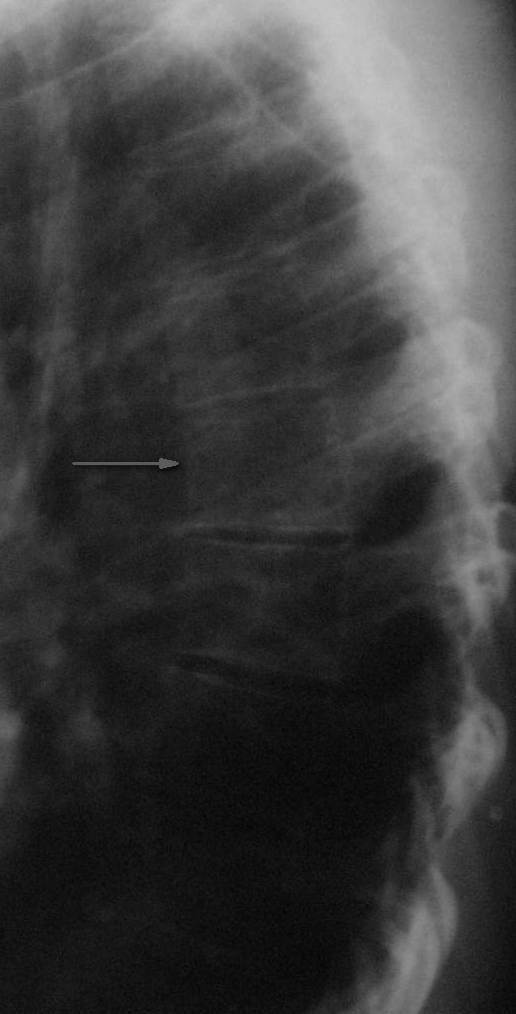

Конечно же можно. Седьмой грудной позвонок указан стрелкой.

По боковой рентгенографии видно клиновидную деформацию не только Т7, но и Т8. Клиновидная форма тела Т7 скорее всего обусловлена саондилодисплазией такой же как и у тела Т8. По нижнему краю тела Т7 четко просматривается склероз замыкательной пластинки, высота диска Т7-Т8 явно снижена по сравнению с Т8-Т9.

Я думаю, рентген картина соответствует перенесенной спондилодисплазии и развивающемуся остеохондрозу на данном уровне и не связанна с травмой.